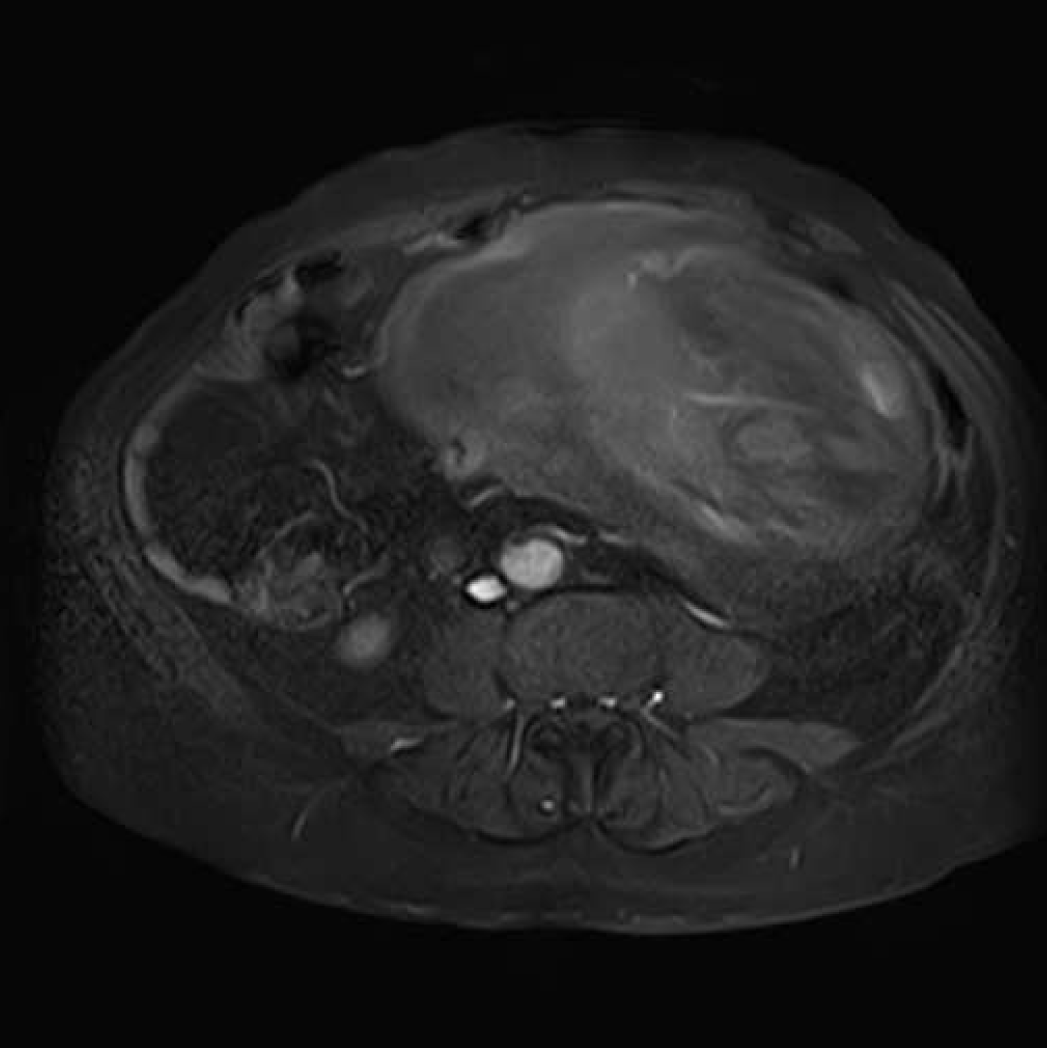

A 59-year-old male patient admitted after he realized a swelling in his abdomen with asthenia, fatigue and abdominal pain complaints for the last few months. In the physical examination, vital findings were normal. In palpation, a mass was detected filling lower left quadrant, and extending to the right of midline and umbilicus. In laboratory examinations, white blood cell (WBC):15.400/mm3, Albumin:2.1 mg/dl and HCV RNA (+). Carcinoembryonic antigen (CEA), CA 15-3, CA 19-9, CA 125 were found to be within normal ranges. In magnetic resonance imaging (MRI) scan, a mass lesion with the size of 25x19 cm, filling the lower half of abdomen, having cystic necrotic areas internally. The mass was well circumscribed and pushed the intestinal segments and mesenteric tissues towards periphery (Figure 1). No finding indicating metastatic disease was found.

Figure 1: Magnetic resonance imaging scan of abdomen.

Abdominal computed tomography (CT) scan and MRI scan may show the association of the mass with adjacent organs and vascular structures, and may provide information about histological type. There are publications recommending abdominal CT scan or MRI scan as ideal method [6] [7] [8]. In our case, the structure of mass and its association with surrounding tissues and adjacent organs were assessed in detail before the operation with MRI.